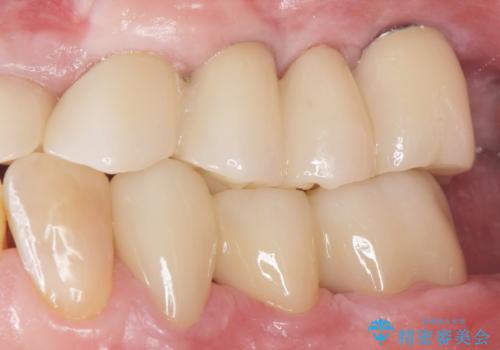

しっかりと咬むことができるようになり、喜んで頂けました。

他院ではお断りされたインプラント治療を行うことができ、ご満足頂けました。

インプラントの種類:ストローマン BLT

被せ物の種類:オールセラミッククラウン ベレッツァ